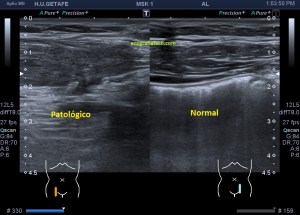

Durante la exploración de una eco de abdomen en el contexto de un paciente que acude por elevación de transaminasas observo una imagen heterogénea, irregular, con una pared marcadamente calcificada, bilobulada de gran tamaño que medí en dos partes ya que me pareció claramente que estaban diferenciadas.

Una de ellas, la primera, era mucho más hiperecogénica y más pequeña, su centro estaba mas calcificado, su sombra acústica posterior era mucho más acuciada y llamaba más la atención. Justo al lado, otra lesión de mayor tamaño, su calcificación era mucho más sutil y más periférica delimitando una LOE hipoecogénica de un tamaño muy importante, adyacente a la más pequeña, como he comentado previamente. Ambas sin señal Doppler.